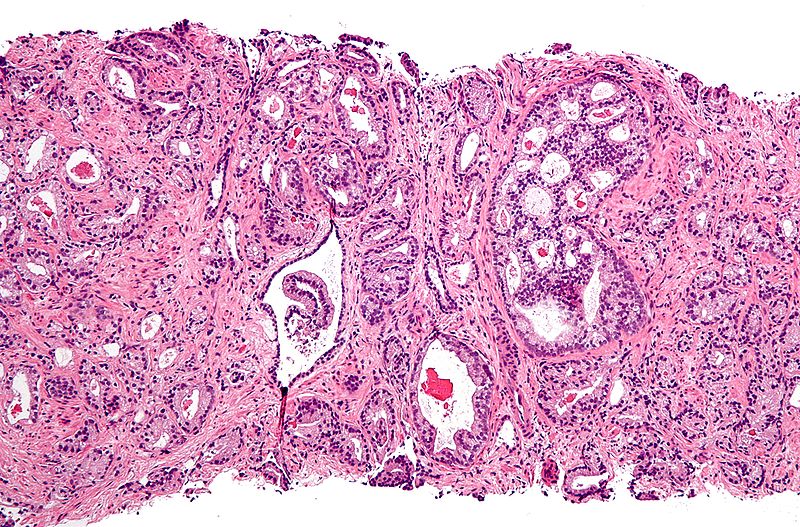

前列腺癌的显微照(来源:维基百科)

在这项研究中,作者们观察了1,033名患有炎症性肠病的男性(实验组)和9,306名未患这种疾病的男性(对照组)。

对这这两组男性进行了长达18年的跟踪后,研究人员发现,患有炎症性肠病的人更容易患前列腺癌和拥有更高的PSA水平。